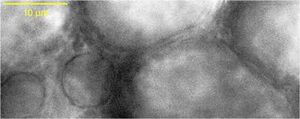

Prof. Seok-Hyun Yun's research group uses Zaber's MVR inverted microscope, which was customized to incorporate an optical path for Brillouin microscopy alongside epifluorescence and brightfield imaging. Brillouin microscopy is an optical technique pioneered in Prof. Yun's lab that allows the stiffness of biological materials to be probed with micron-scale spatial resolution, providing insight into biological processes which are modulated by local mechanical changes. Dr. Amira Eltony, lab post-doc and microscope builder, and other researchers are using the new microscope to perform imaging and map the biomechanical properties of cells and tissue sections.